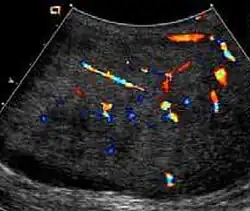

At ultrasound, the findings of acute epididymitis include an enlarged hypoechoic or hyperechoic (presumably secondary to hemorrhage) epididymis [Fig. 20a]. Other signs of inflammation such as increased vascularity, reactive hydrocele, pyocele and scrotal wall thickening may also be present. Testicular involvement is confirmed by the presence of testicular enlargement and an inhomogeneous echotexture. Hypervascularity on color Doppler images [Fig. 20b] is a well-established diagnostic criterion and may be the only imaging finding of epididymo-orchitis in some men.

Doppler ultrasound of epididymitis, seen as a substantial increase in blood flow in the left epididymis (top image), while it is normal in the right (bottom image). The thickness of the epididymis (between yellow crosses) is only slightly increased (7 mm).

Doppler ultrasound of the scrotum of the same case, in the axial plane, showing orchitis (as part of epididymo-orchitis) as hypoechogenic and slightly heterogenic left testicular tissue (right in image), with an increased blood flow. There is also swelling of peritesticular tissue.